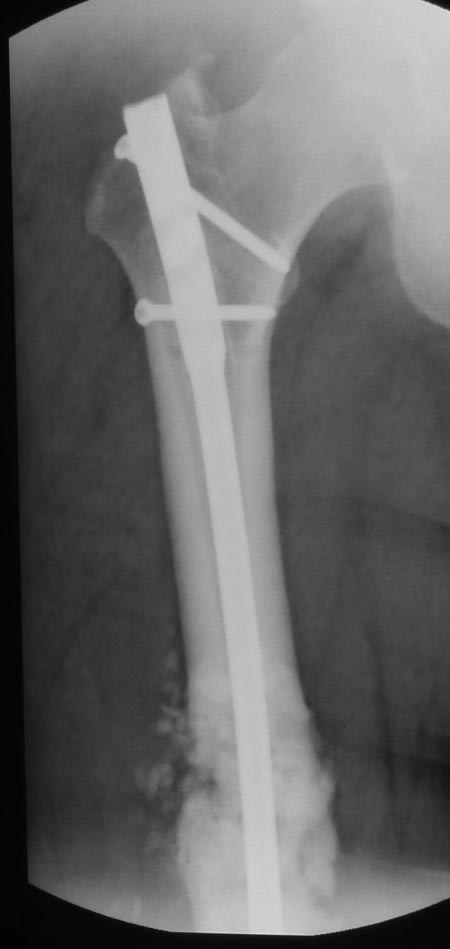

Уважаемые коллеги. Хотелось бы выслушать мнения и советы по представленному случаю. Пациент 42 лет, вес 130 кг, рост около 160 см, сахарный диабет в легкой форме (впервые выявлен после травмы). Травма в феврале 2011 г. - упал с мотоцикла на отдыхе за рубежом. По возвращении в Россию был прооперирован в несколько этапов: в марте 2011 г. - остеосинтез обеих костей правого предплечья пластинами по поводу открытого перелома; интрамедуллярный остеосинтез правого бедра; остеосинтез проксимального конца правой большеберцовой кости. В апреле 2011 г. был доставлен 1 блокирующий винт в дистальное отверстие гвоздя и выполнена пластика крестообразных и наружной боковой связок левого коленного сустава. В феврале 2012 г. были удалены фиксаторы с проксимального конца правой большеберцовой кости и выполнена пластика крестообразных и наружной боковой связок правого коленного сустава. За это время пациент смог начать ходить, сначала с костылями, а затем - без дополнительной опоры. Летом 2013 г. решил укрепить ноги с помощью подъемов пешком на пятый этаж. В результате - усталостная рефрактура правого бедра и перелом интрамедуллярного гвоздя. 09.09.2013 - реостеосинтез латеральным бедренным гвоздем с пластикой костной аутостружкой + СhronoS. Сейчас, через 6 мес после операции, может ходить без дополнительной опоры, периодически беспокоит болезненность в области правого бедра. На сегодняшних КТ - отсутствие признаков консолидации. Нужно ли что то делать и, если да, то что? Рассматриваемые варианты: повторная костная пластика дефекта; доставить блокирующие винты (самый проксимальный винт был удален через 3 мес после операции). Еще раз менять гвоздь не хотелось бы. На представленных снимках: бедро в 2011 г., через несколько мес после операции; в 2012 г., на стадии консолидации; со сломанным гвоздем; сразу после повторной операции (3 рентгенограммы). Все КТ - сегодняшние. Заранее спасибо за ответы.

Костная пластика делалась стружкой из фрагментов большого вертела: верхний конец предыдущего гвоздя был погружен в него на пару см (первый гвоздь ставился не у нас, я только доставил второй дистальный блокирующий винт)и гранулами СhronОs. Учитывая совершенно необъятные размеры бедра, удаление сломанного гвоздя получилось достаточно травматичным. Пришлось широко открываться проксимально, на уровне перелома и дистальнее, чтобы сформировать окошко для выбивания дистального отломка гвоздя (дистальный конец гвоздя не имел отверстия). После операции около месяца собиралась жидкость в области большого вертела (серома), на фоне пункций постепенно ушла. Поэтому и хотелось бы избежать еще одного вмешательства на уровне большого вертела.